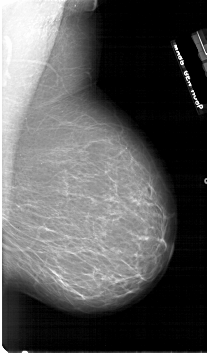

Жирная (не плотная) грудь

Умеренно плотная грудь

Плотная грудь

Маммограммы представляют собой изображения структур, проецируемых на плоскость: плотная грудная маммограмма, следовательно, состоит из многих других структур, которые необходимо проанализировать, чем более жирная, пустая грудь. По этой причине диагностировать рак молочной железы труднее для моложе, чем для пожилых женщин.

Нажмите на миниатюрные картинки, чтобы получить увеличенный размер.